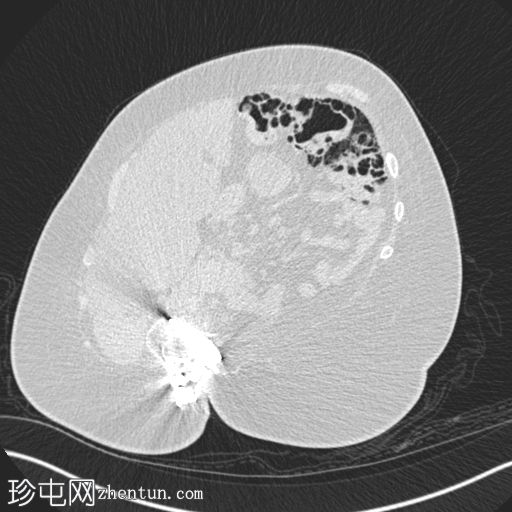

结肠囊状积气

横结肠壁一小段可见多个圆形囊状气体密度影。无肠壁积气。

无周围炎症条索影。

无气腹或门静脉积气。

经皮内镜下胃造瘘术(PEG)已进入胃内。

脊柱侧弯,并植入脊柱固定棒。

本例为节段性结肠囊状积气,局限于横结肠。

该患者全身状况良好,病因不明,且随访数月后影像学表现未见变化。

未发现任何典型的肠壁积气病因。文献中很少报道正压/有创通气与气肿之间存在关联(尤其是在肺气肿患者中,而这位患者并没有肺气肿),但这种关联可能更为广泛,并且会随时间推移而变化。我查阅文献后发现,关于无创通气与肺气肿之间关联的报道并不多见。